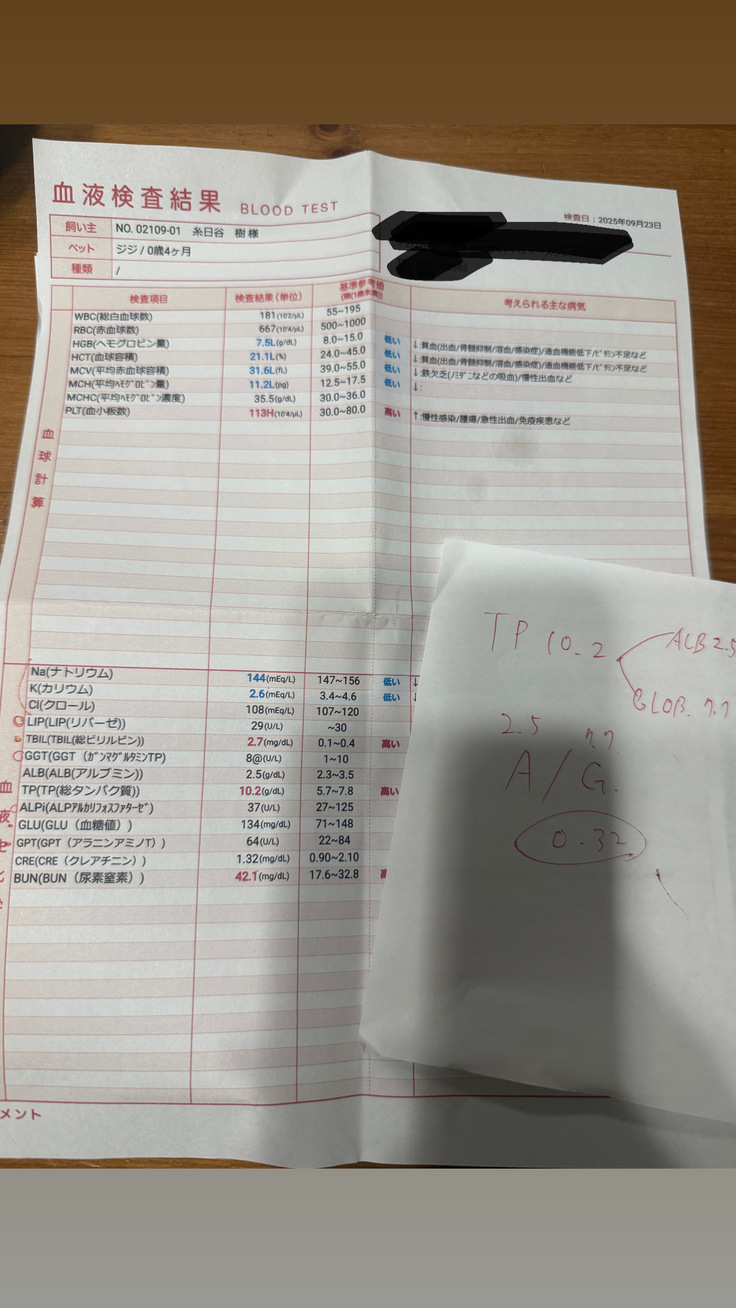

すぐに血液検査など詳しい検査をしていただき、出た結果です。

タンパク質からの計算式に基づいて、この時点でおそらくFIPで間違いないだろうとの診断でした。

そして詳細の検査の結果、9/26、正式にFIP(Wetタイプ)と診断を受けました。